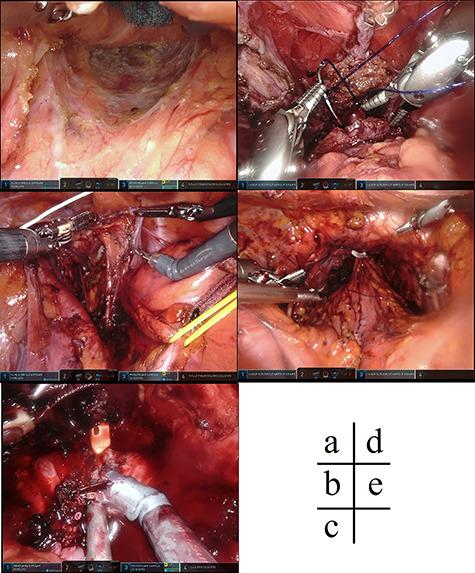

直肠癌和前列腺病变的同步机器人辅助手术。

Simultaneous robot-assisted surgery for rectal cancer and prostatic lesions.

Robotic surgery has become prevalent in many departments all over the world because of its usefulness. It is used in many cases, as well as in gastrointestinal surgery, which treats the rectum as pelvic surgery, urology and gynecology. We experienced two cases of joint surgery, with urology as pelvic surgery. The patient underwent robot-assisted low anterior resection, combined prostate resection and ileostomy for prostate invasion of rectal cancer. He was discharged without any complications. Robotic surgery was considered to be useful in surgery to manipulate the same area. In addition, it was considered that smoother and safer surgical procedure could be possible by conducting preoperative meetings with the participating departments.

摘要

由于其实用性,机器人手术在世界各地的许多科室已变得很普遍。它被用于许多病例,包括胃肠外科(将直肠手术视为盆腔手术)、泌尿外科和妇科。我们经历了两例联合手术,其中泌尿外科手术作为盆腔手术。该患者接受了机器人辅助低位前切除术、联合前列腺切除术以及因直肠癌侵犯前列腺而行的回肠造口术。他出院时没有任何并发症。机器人手术被认为在操作同一区域的手术中很有用。此外,通过与参与科室召开术前会议,认为可以实现更顺畅、更安全的手术过程。